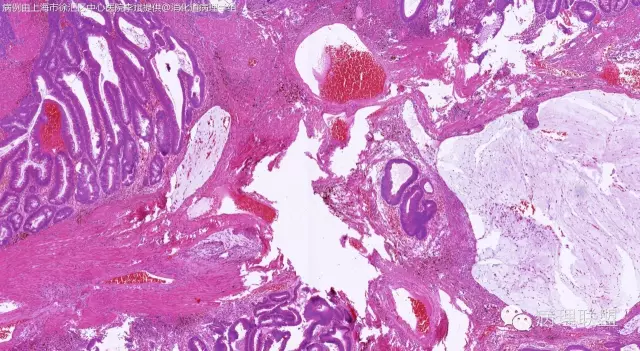

男,64岁,距肛门口45cm息肉大体:灰白结节2*2*1cm(病例由上海市徐汇区中心医院 李斌 提供,致谢!)

管状~绒毛状腺瘤伴低级别上皮内瘤变,黏膜下层部分腺体破裂黏液外溢伴黏液糊形成。

本例部分腺体异位到黏膜下层。

@李斌 李大夫的片子一向漂亮,有赏心悦目的感觉,必须赞一个。这例同意周大夫的意见,低级别绒毛管状腺瘤伴腺体破裂导致的黏液外溢。粘液池周围可见血管扩张淤血、含铁血黄素沉积、肉芽组织形成,提示发生过蒂扭转和出血,这常是造成假浸润、粘液溢出的原因。比较大的绒毛管状腺瘤会有分叶结构,会有比较粗大的平滑肌干,但缺少P-J息肉叶脉样从主干再分支出来的细平滑肌束。作为错构瘤性息肉的一种,P-J息肉的腺体可以分支、扩张、腺腔不规则,但没有细胞异型性,伴发异型增生时,局部出现细胞异型性但不会像这例这样齐刷刷都是异型的腺体。